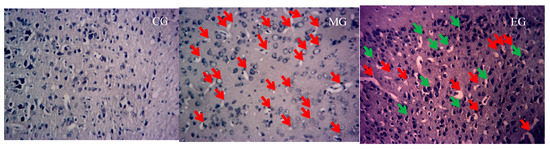

3.2. The Changes of Nissle Body in the Hippocampus

| Group | CA1 (Number) | CA3 (Number) | Nissl Bodies (Number) |

|---|---|---|---|

| CG | 56.8 ± 6.6 | 31.3 ± 8.6 | 81.3 ± 15.6 |

| MG | 55.5 ± 4.9 | 22.7 ± 9.3 ** | 51.0 ± 17.9 ** |

| EG | 55.2 ± 5.8 | 29.6 ± 7.0 ## | 72.6 ± 14.5 # |